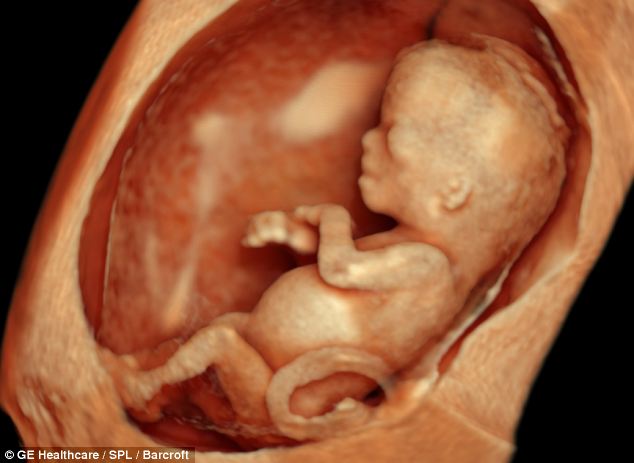

12 Weeks Fetus High Resolution Stock Photography And Images Alamy